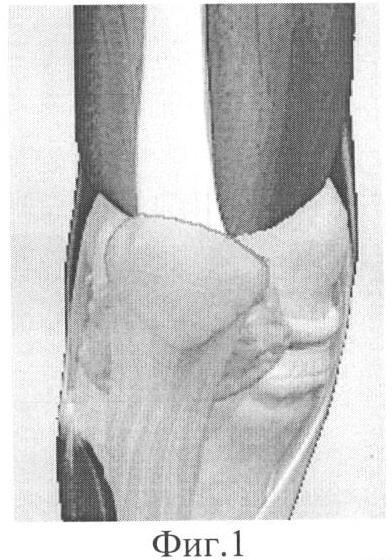

Предлагаемый способ иллюстрируется следующими чертежами: на фиг.1 изображено состояние m. vastus medialis obliquus до операции; на фиг.2 – проведение шовных нитей и их окончательное расположение перед натяжением под артроскопическим контролем; на фиг.3 – окончательный вид после затягивания нитей по достижении конгруэнтности пателлофеморального сочленения.